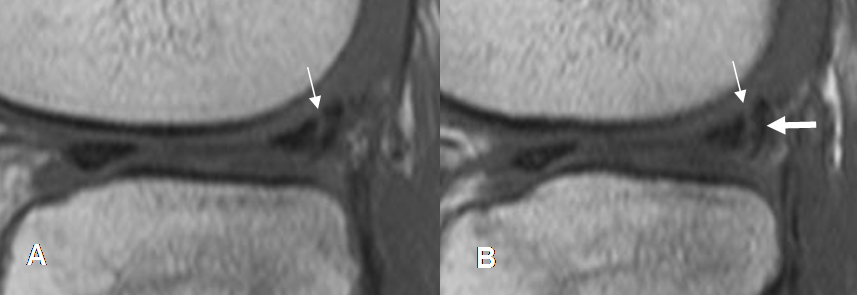

Fig 78. Ruptura meniscal en asa de cubo.

A y B: RM sagital en T2. Signo clásico del doble LCP, por ruptura en asa de cubo. LCP normal (Flecha gruesa) y menisco desplazado (Flecha delgada).

Fig 79. Ruptura meniscal en asa de cubo.

A y B: RM coronal en STIR. Fragmento meniscal ocupando la región intercondilea, por ruptura en asa de cubo. LCP normal (Flecha gruesa) y menisco desplazado (Flecha delgada).